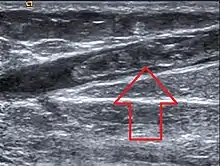

| Ultrasonographic image showing thrombosis of the great saphenous vein. | |